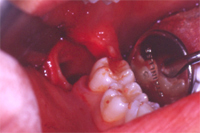

Abb. 3 zeigt die Situation direkt nach Entfernen des Zahnes. Die Wundheilung erfolgte absolut problemlos. Zwei Monate später ist kaum noch zu sehen, dass doch ein recht massiver zahnchirurgischer Eingriff stattgefunden hat (Abb. 4).